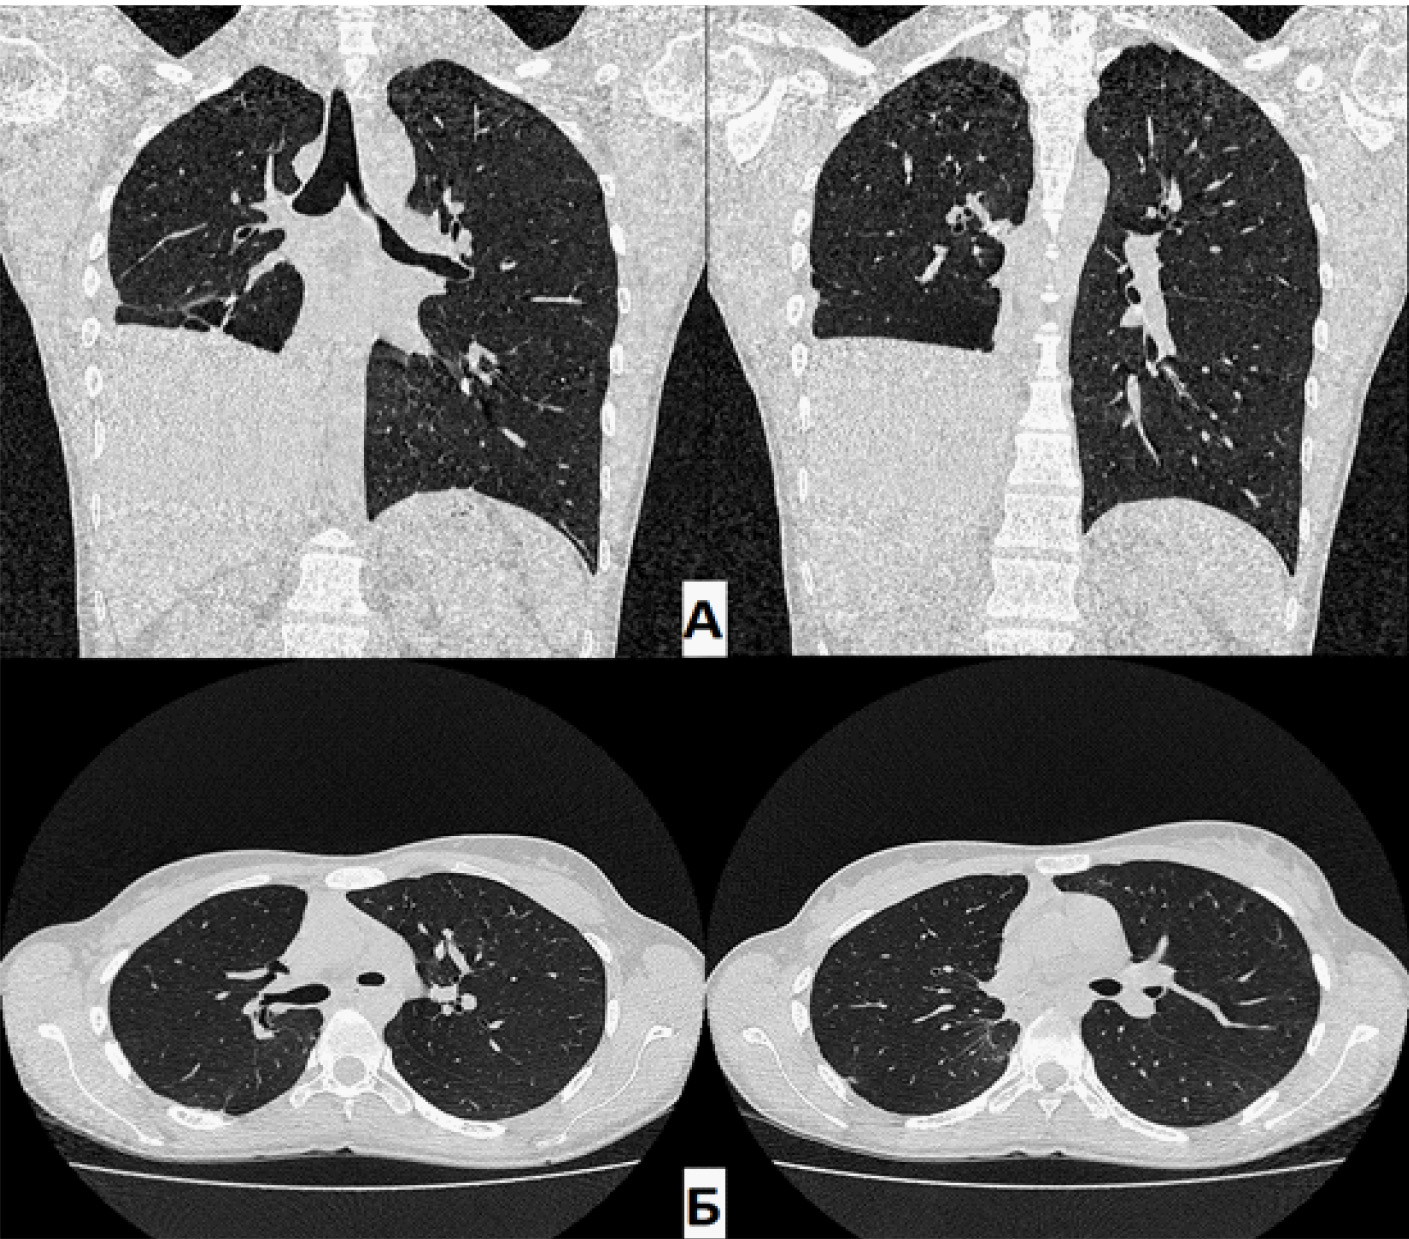

На КТ органов грудной клетки (от 21 июня 2021 г.) определялось бронхоплевральное сообщение культи правого промежуточного бронха с плевральной полостью. Остаточная плевральная полость (ОПП) в нижних отделах справа. В оставшихся отделах правого легкого – без патологических изменений (очаговых и инфильтративных теней не обнаружено). Тень средостения располагается срединно, правый купол диафрагмы приподнят до уровня VI межреберья (рис. 1).

Рис. 1. Компьютерная томография (А – фронтальная проекция; Б – аксиальная проекция) при поступлении. Определяется остаточная полость парамедиастинально слева